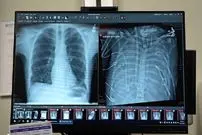

مردی ۴۸ ساعت بدون ریه زنده ماند

یک مرد ۳۳ ساله بعد از اینکه گروه پزشکی، اعضای بدنش را با یک سیستم ریه مصنوعی خارجی جایگزین کردند که توسعه یافته بود تا…